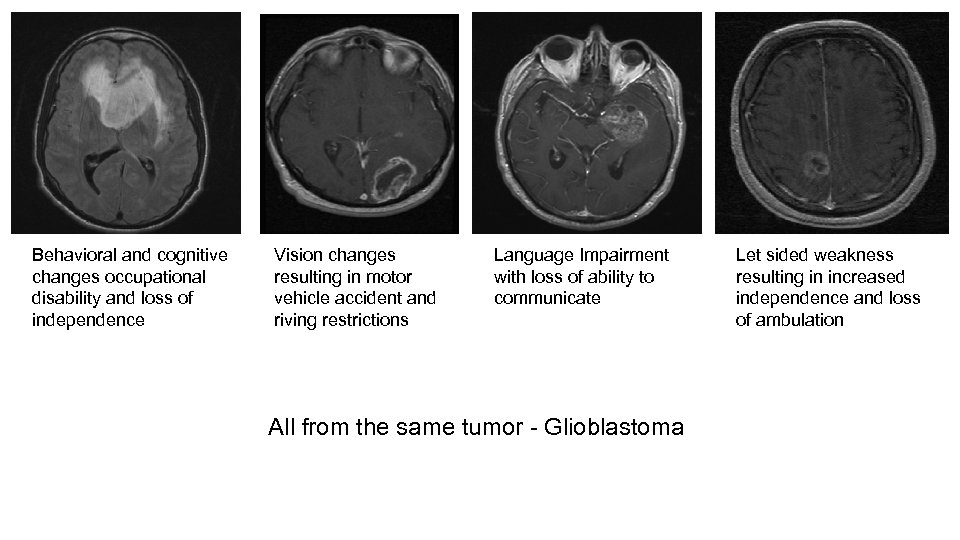

Behavioral and cognitive changes occupational disability and loss of independence Vision changes resulting in motor vehicle accident and riving restrictions Language Impairment with loss of ability to communicate All from the same tumor - Glioblastoma Let sided weakness resulting in increased independence and loss of ambulation